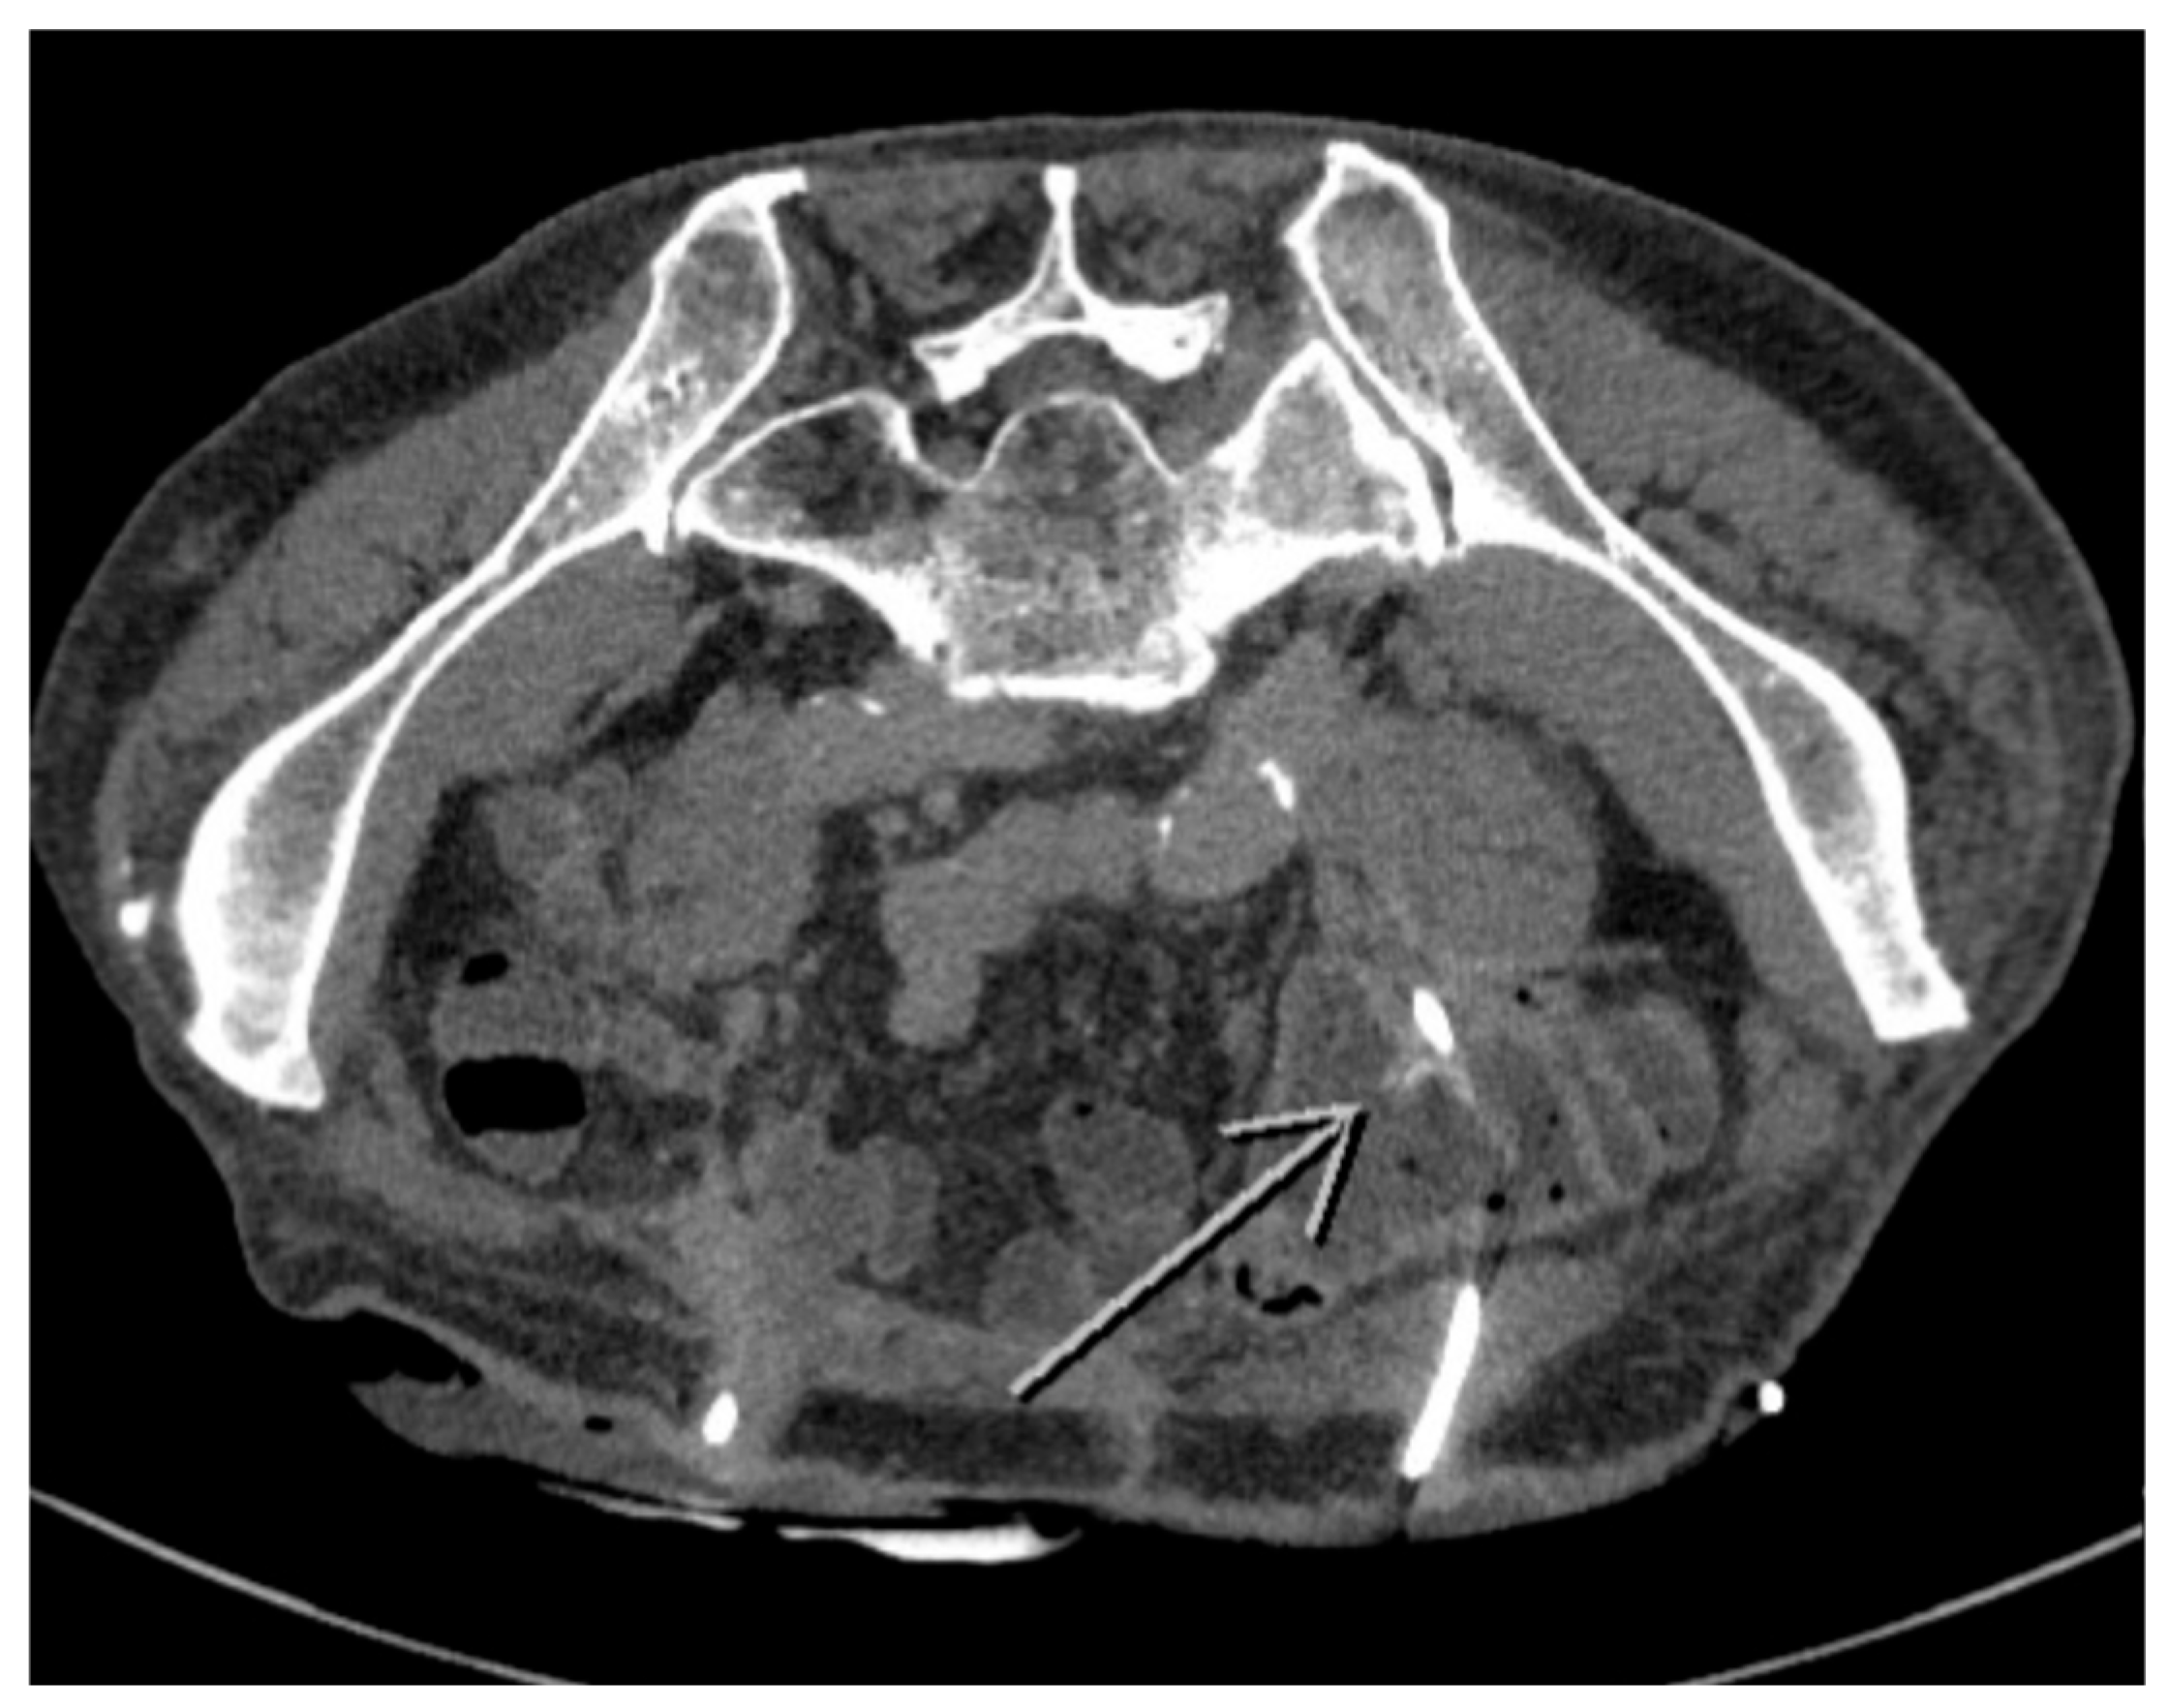

2. Case Presentation

2.1. Patient Characteristics and Clinical Findings

2.2. Treatment